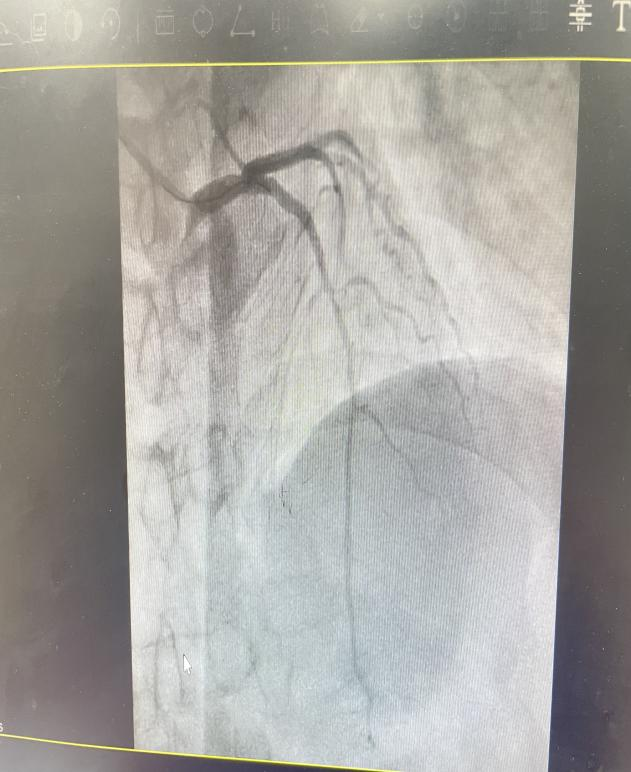

在急诊科初步稳定病情后,心内科团队迅速介入,评估黄叔叔病情并决定立即进行冠脉造影及PCI术以开通闭塞血管。9时48分, 导丝成功穿越患者前降支近段病变处及其远端病变血管进行预扩张时,突发紧急情况!黄叔叔术中出现再灌注恶性心律失常,即室颤,随即失去意识。面对这一危急状况,心内科团队迅速果断实施200焦耳电击除颤,成功使患者室颤转复。然而,在准备支架植入之际,黄叔叔再次陷入室颤危机,心内科团队立即再次进行除颤,同时,护士也迅速建立三路静脉通道,确保抢救药物及时输入。期间,黄叔叔心率波动剧烈,多次在室颤与心动过缓间反复,医护人员通过反复除颤及抢救药物推注等措施,随着前降支支架的成功植入,患者血管畅通,神志逐渐恢复,心率上升,心律终恢复窦性,室颤未再复发。

血管开通前后对比图